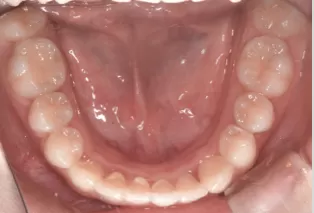

Photos intra-orales